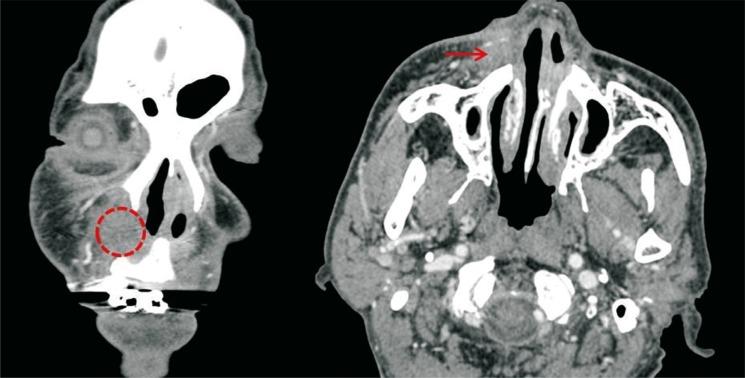

An odontogenic cutaneous fistula is a pathological communication between the outer skin surface of the face and the oral cavity. Facial cutaneous fistula is a complication of odontogenic infection that is often misdiagnosed with skin infection. We report a rare case, which was diagnosed as basal cell carcinoma based on the biopsy of skin lesions in the patient who had been diagnosed with odontogenic cutaneous fistula. A 64-year-old male patient presented with a cutaneous odontogenic fistula. The patient had undergone surgical extraction of fistula tract and loose tooth before dermatology or plastic surgery consultation. With the biopsy and computed tomography, it was confirmed that fistula and basal cell carcinoma. However, the connection between the fistula and skin cancer was not clear. Positron emission tomography-computed tomography scan was performed and was not detected as other local or distant metastasis. After that, wide excision of the skin lesion was performed. Although skin cancer is not commonly observed, it is necessary to rule out this disease entity by performing biopsy of skin lesions.

牙源性皮肤瘘是面部皮肤外表面与口腔之间的病理性通道。面部皮肤瘘是牙源性感染的一种并发症,常被误诊为皮肤感染。我们报告一例罕见病例,该病例在被诊断为牙源性皮肤瘘的患者中,根据皮肤病变活检被诊断为基底细胞癌。一名64岁男性患者出现牙源性皮肤瘘。在咨询皮肤科或整形外科之前,该患者已接受瘘管和松动牙齿的手术拔除。通过活检和计算机断层扫描,证实为瘘管和基底细胞癌。然而,瘘管与皮肤癌之间的联系尚不清楚。进行了正电子发射断层扫描-计算机断层扫描,未检测到其他局部或远处转移。此后,对皮肤病变进行了广泛切除。虽然皮肤癌并不常见,但有必要通过对皮肤病变进行活检来排除这种疾病。